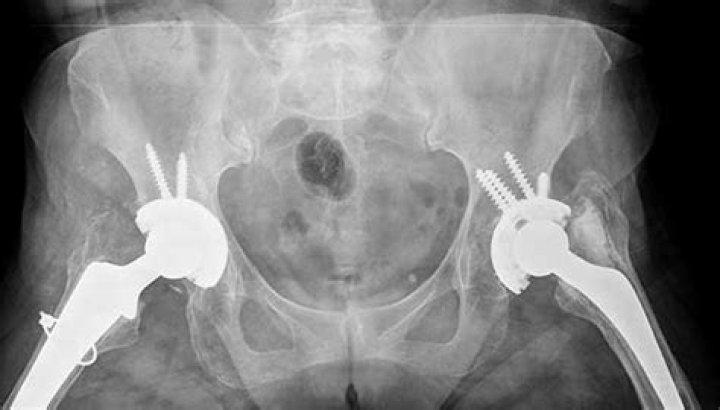

Which is better hip pinning or hip replacement?

A hip replacement can prevent problems such as arthritis that may happen because of avascular necrosis. Hip pinning is a treatment choice in younger adults and children. It’s also good for hip fractures that happen between the greater and lesser trochanter (intertrochanteric fractures).